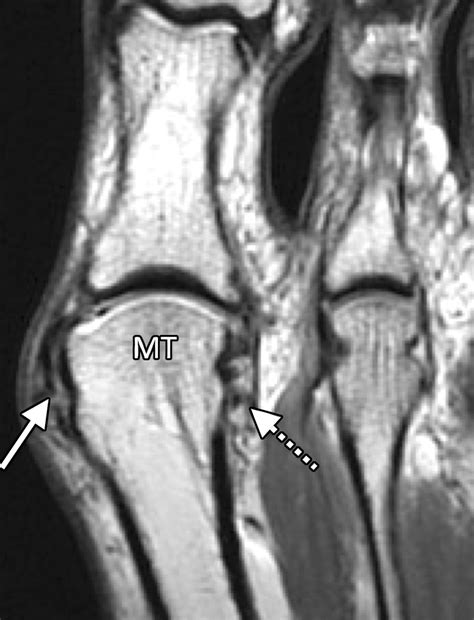

Diagnosing Mtp Joint Pain

Diagnosing Mtp joint pain typically involves a combination of physical examination and diagnostic tests. A healthcare provider will:

• Order imaging tests, such as X-rays, MRI, or CT scans, to visualize the joint and surrounding structures.